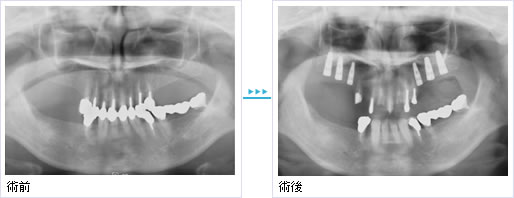

全顎的治療を希望して来院されました。できるだけ残せる歯は残し、上顎に3本、下顎に1本のインプラントを用い治療を行いました。